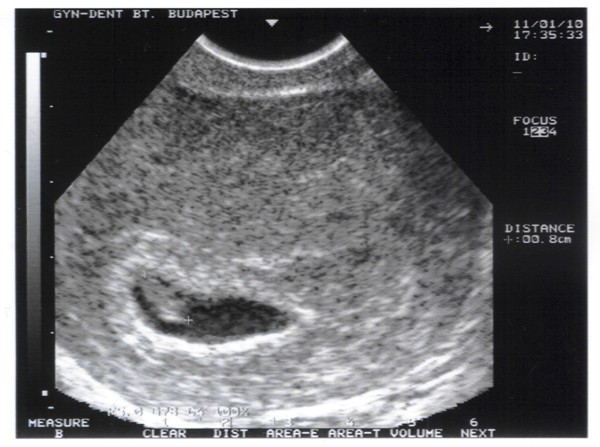

Zsuzsám! Még egyszer gratulálok! Nagyon szép kis petezsákocskát láthatunk az UH képen... Sajnálom, hogy a doki nem kapcsolta be a szívdobit, de talán majd legközelebb hallhatjátok. Nagyon jó lett a vonalzód, csak az a kár, hogy nem magyar a felírat :S. Sikerült végül a doki kérdéssel közelebb kerülnöd a megoldáshoz?? Puszi és simi a Manókának!